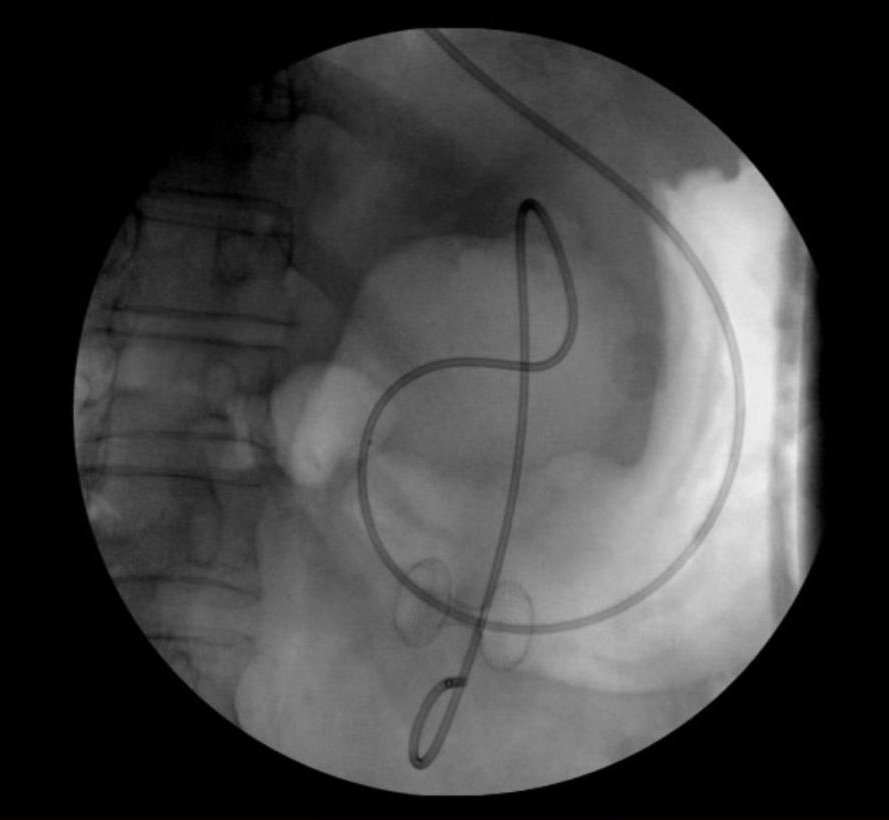

术后胃腔内支架影

在与患者及家属充分沟通后为其实施“超声内镜引导下胰腺包裹性坏死穿刺引流术+支架置入术”,术中,支架顺利释放,大量褐色囊液涌入胃内。术后复查显示,囊腔明显缩小。